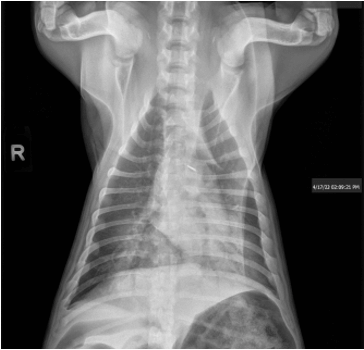

3 view chest radiographs performed at primary care veterinarian on 4/17/23:

Severe symmetrical caudal dorsally distributed alveolar pulmonary infiltrates consistent with non cardiogenic pulmonary edema secondary to reported near drowning event.

Subjective microcardia may represent hypovolemia.

Gas filled stomach and small bowel consistent with aerophagia.

Evie’s respiratory rate and effort continued to improve. The butorphanol was discontinued and she was acting like a normal puppy. Recheck radiographs showed persistent but slightly improved non cardiogenic pulmonary edema. She was transitioned from high flow oxygen to an oxygen cage at 40%. She ate well and was very energetic. Overnight she was trialed on room air and continued to breath with a normal respiratory rate and effort and was discharged the following morning.